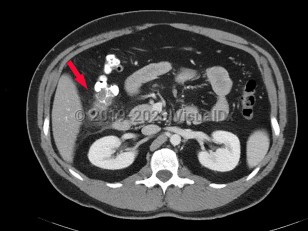

Biliary calculus